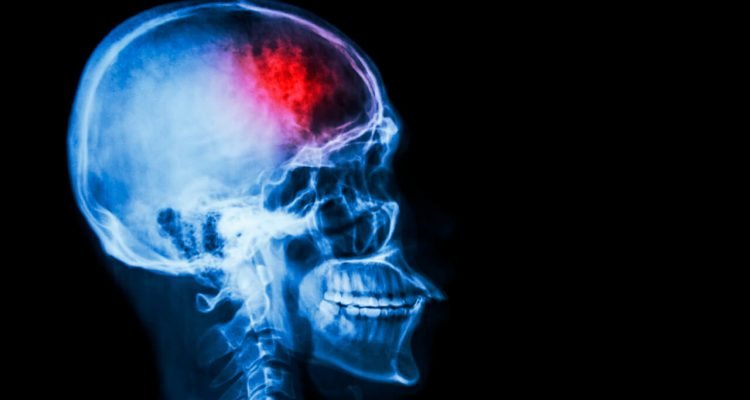

Insultas – tai ūmus smegenų aprūpinimo krauju sutrikimas. Kai kraujas nustoja pernešti rūgštį į ląsteles, jos pradeda žūti. Viena iš labiausiai paplitusių insulto rūšių yra išemija. Viena iš jo priežasčių gali būti atitrūkęs kraujo krešulys: jis užkemša kraujagyslę ir trukdo kraujotakai.